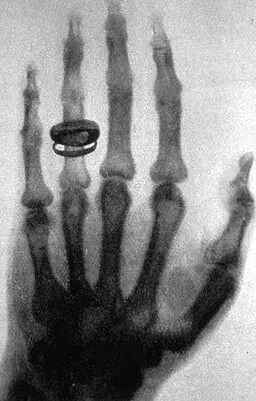

Vůbec prvním snímkem, který měl vědec pomocí neznámého záření zachytit, byla ruka jeho manželky Anny Berthy Röntgenové, kde byly jasně viditelné kosti a její prsteny. Když se na něj podívala, údajně vykřikla: „Právě jsem viděla svou smrt!“ Převratný objev ji vylekal natolik, že do laboratoře svého muže od té doby odmítala v obavách vstoupit.